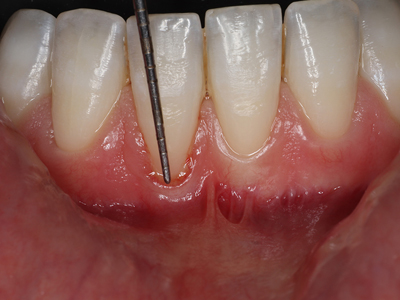

Periodontics

A periodontist is a dental specialist who focuses on the prevention, diagnosis, and treatment of gum disease (periodontal disease) and other conditions affecting the gums, jawbone, and other supporting structures of the teeth. They perform treatments such as deep cleanings (scaling and root planning), gum grafts, and bone and tissue regeneration. Periodontists also specialize in placing dental implants to replace missing teeth.